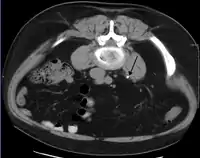

اکثر سنگها به دلیل ترکیبی از عوامل ژنتیکی و محیطی شکل میگیرند. عوامل خطر شامل کلسیم بالای ادرار، چاقی و کمتحرکی، غذاهای خاص، برخی داروها، مکملهای کلسیم، هیپرپاراتیروئیدیسم، نقرس و نوشیدن مایعات ناکافی است. سنگها در کلیه به خاطر غلظت بالای مواد معدنی در ادرار تشکیل میشوند. تشخیص معمولاً بر اساس علائم، آزمایش ادرار و تصویربرداری پزشکی است. آزمایش خون همچنین ممکن است مفید باشد.[2] سنگها بهطور معمول براساس موقعیت آنها طبقهبندی میشوند: سنگ کلیه (nephrolithiasis)، سنگ مجاری (ureterolithiasis)، سنگ مثانه (cystolithiasis). طبقهبندی دیگر بر اساس مادهای است که سنگ از آن تشکیل میشود: اگزالات کلسیم، اسید اوریک، استرویت، سیستین؛ البته اغلب سنگها از جنس کلسیم اُگزالات هستند.[1]

تشخیص[6]

اگر یک یا چند مورد از علائم ذکر شده را در خود مشاهده میکنید، باید به پزشک متخصص اورولوژی مراجعه کنید. پس از انجام آزمایشهای تخصصی، وجود یا عدم وجود آن، توسط پزشک تشخیص داده شده و سایر اقدامات لازم برای شما تجویز خواهد شد.